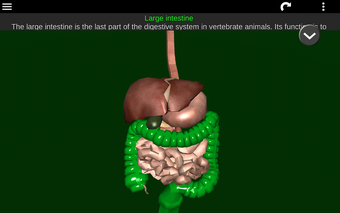

Diese Anwendung zeigt ein dreidimensionales Modell der menschlichen Körperorgane und eine Beschreibung aller von ihnen.

Sie können jedes Organ wie Herz, Gehirn, Lunge, Fortpflanzungssystem, Leber, Darm, Eierstock, Hoden, Magen, Niere usw. anfassen.

Sie ist für alle Menschen nützlich, auch für Studenten, da jedes Anatomieorgan in einer anderen Farbe dargestellt ist.

Sie können die App verwenden, um herauszufinden, welches die verschiedenen Körperorgane sind und welche Funktionen sie haben.